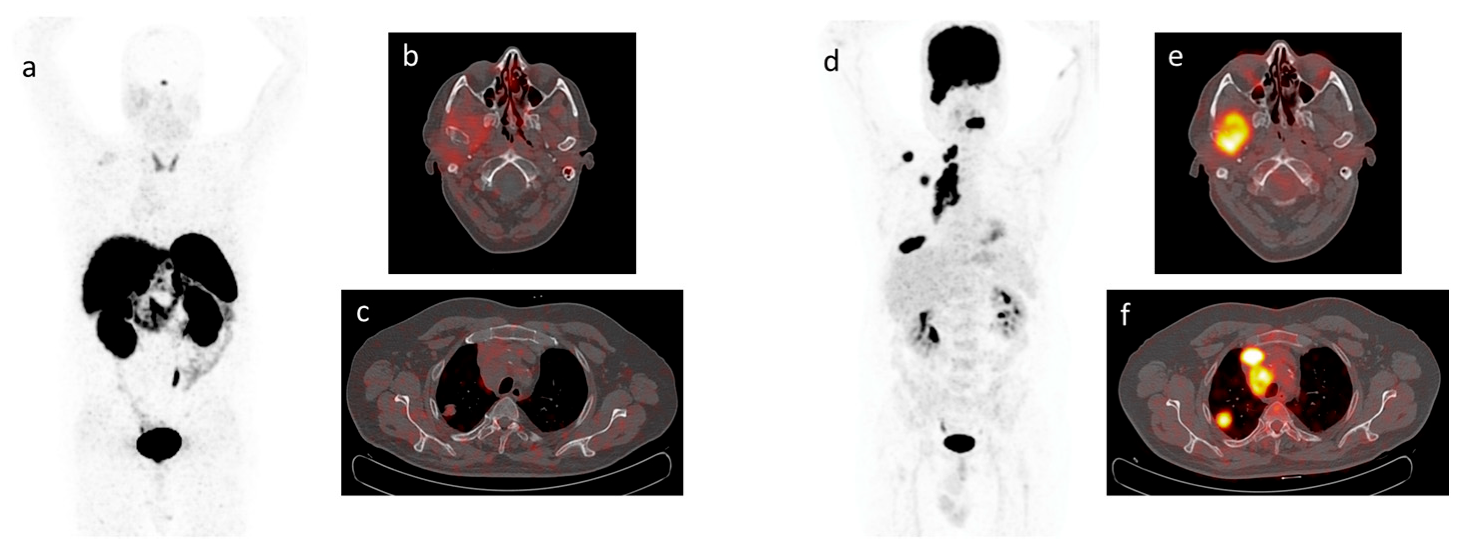

4. Functional Imaging by SST Analogs

5. Imaging Analysis

6. Functional Imaging by 18F-FDG PET/CT